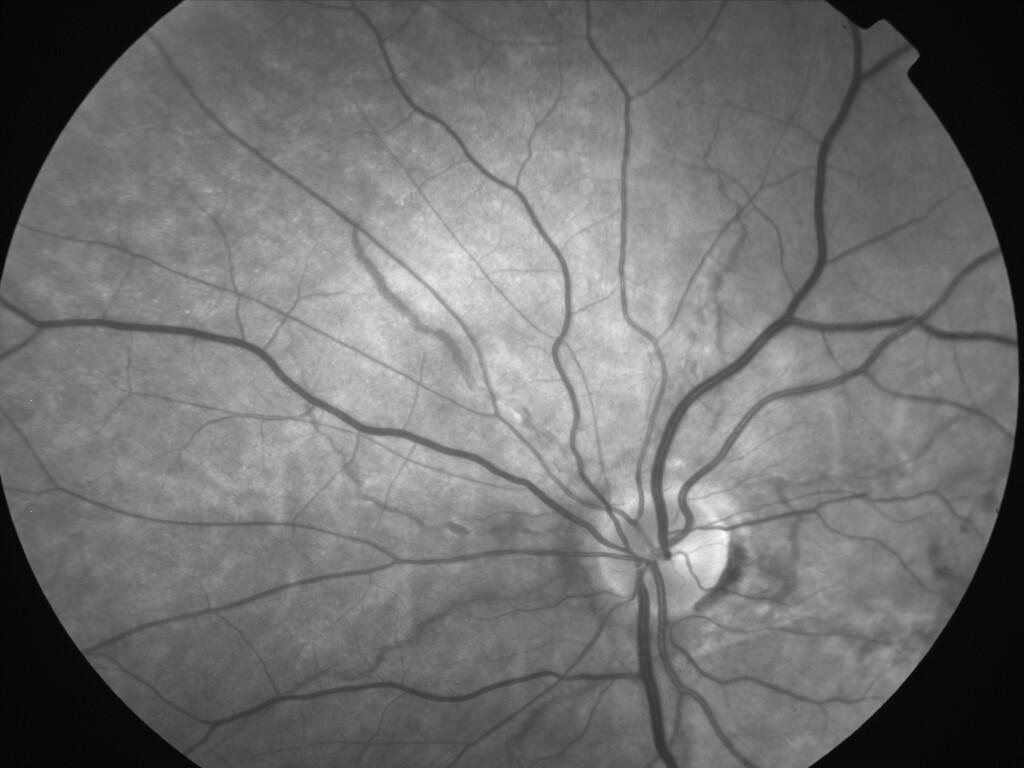

ASSOCIATION STRIES ANGIOIDES ET DYSROPHIE MACULAIRE RETICULEE

NEOVASCULARISATION